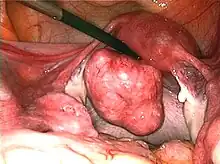

Uterine fibroids as seen during laparoscopic surgery

Fibroids are a type of uterine leiomyoma. Fibroids grossly appear as round, well circumscribed (but not encapsulated), solid nodules that are white or tan, and show whorled appearance on histological section. The size varies, from microscopic to lesions of considerable size. Typically lesions the size of a grapefruit or bigger are felt by the patient herself through the abdominal wall.[1]